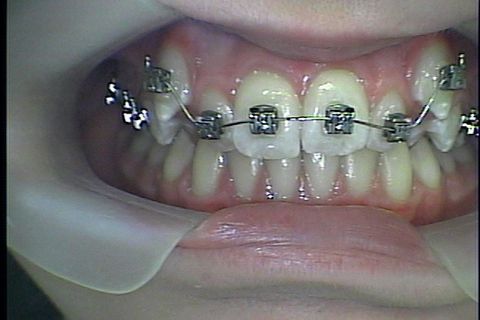

Antes da colocaçao de aparelho fixo

Montagem de fixo